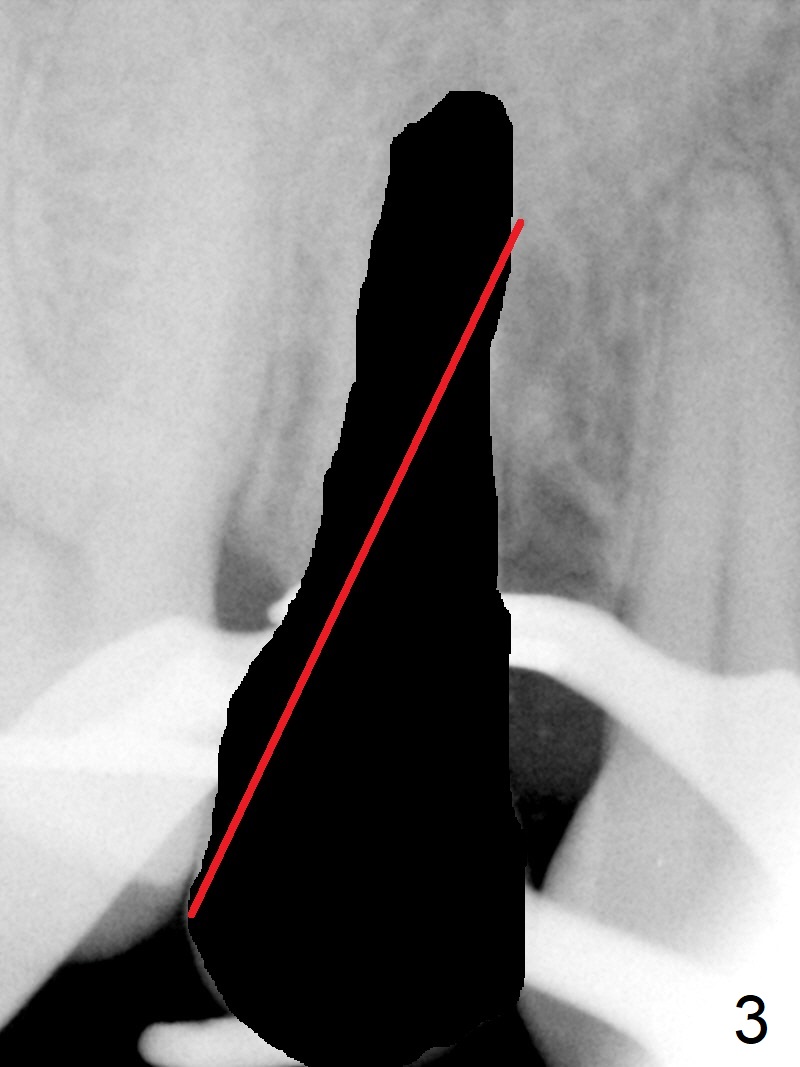

Seven years post RCT (Fig.1), the tooth #4 of a 65-year-old woman fractures subgingival palatally (Fig.2). Since the root of the affected tooth is close to the tooth #3, osteotomy is established in the mesial slope of the socket (Fig.3). Change the trajectory once the drill has penetrated the lamina dura of the socket (Fig.4). The initial depth will be 20 mm for a 3.8x16 mm implant (Fig.5).